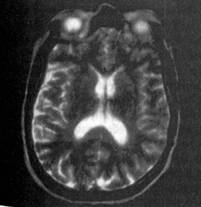

Рис. 2.3. МРТ головного мозга пациента с сосудистой деменцией. Множественные лакунарные инфаркты (7), симметричное расширение боковых желудочков (2), перивентрикулярный (3) и субкортикальный (4) лейкоареоз.

Наличие сосудистых изменений на KT или МРТ головного мозга является обязательным для подтверждения сосудистой этиологии когнитивных нарушений. При этом наиболее надежным диагностическим признаком являются инфаркты мозга, которые проявляются в виде различного диаметра кист («завершенные инфаркты») или очаговых изменений белого и серого вещества без формирования кисты («незавершенные инфаркты»). Диффузные изменения белого вещества (лейкоареоз) также чаще всего отражают наличие сосудистой мозговой недостаточности, но в небольшом числе случаев могут быть следствием дисметаболических, инфекционных, ликвородинамических, инволютивных и других патологических процессов (рис. 2.3).

Как уже отмечалось выше, локализация структурных или функциональных изменений зависит от конкретной нозологической формы нейродегенеративного процесса. Так, для болезни Альцгеймера характерно преимущественное поражение глубинных отделов височных долей (атрофия гиппокампа) и коры теменных долей головного мозга (см. рис. 2.1). При деменции с тельцами Леви отмечается значительное расширение задних рогов боковых желудочков, что свидетельствует о теменно-затылочной атрофии (рис. 2.4). Лобно-височная дегенерация характеризуется атрофией лобных и передних отделов височных долей головного мозга, часто только с одной или преимущественно с одной стороны (рис. 2.5).

Рис. 2.4. МРТ головного мозга пациента с деменцией с тельцами Леви. Расширение боковых желудочков, максимально выраженное в области задних рогов.

Рис. 2.5. МРТ головного мозга пациента с лобно-височной дегенерацией. Атрофия коры лобных долей головного мозга (белая стрелка), больше слева, внутренняя гидроцефалия (черная стрелка).